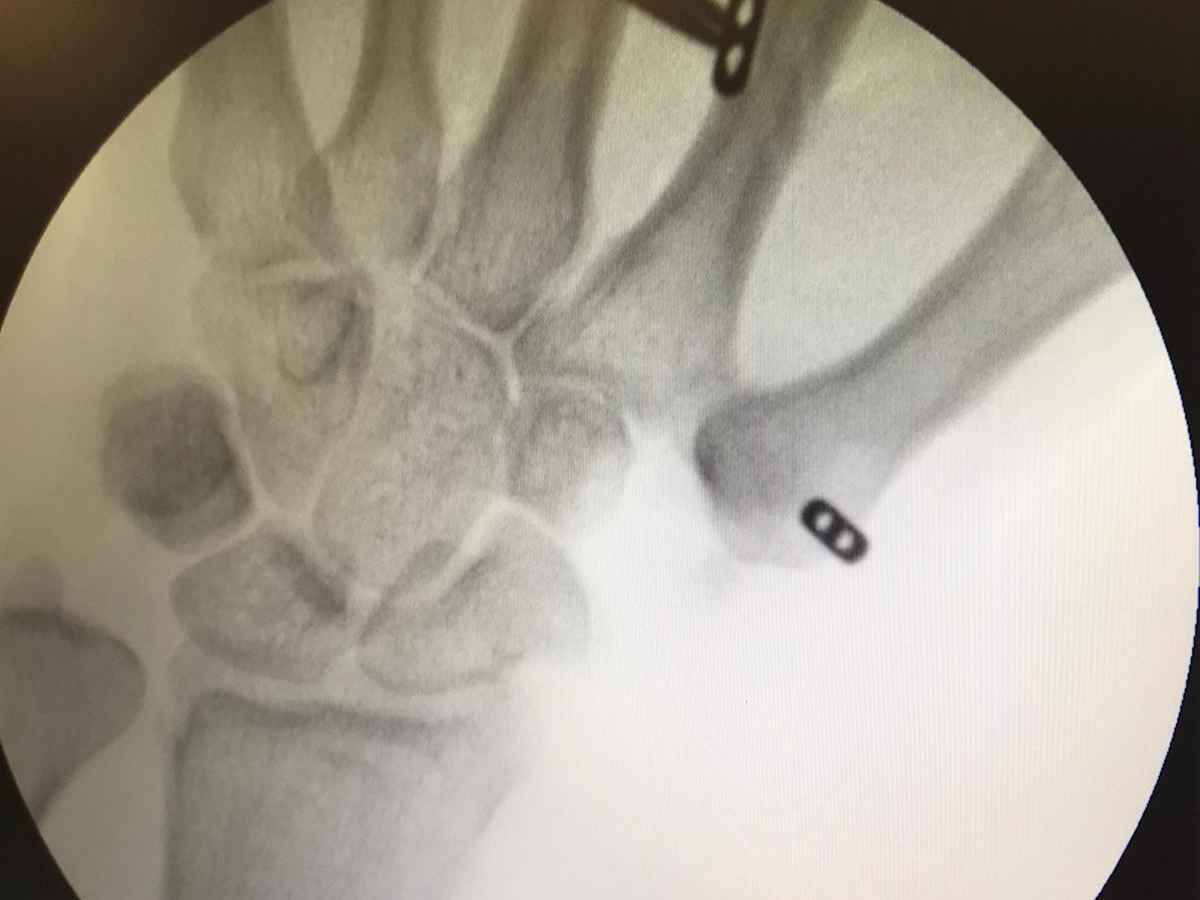

La rizartrosis es una alteración degenerativa de la zona que se encuentra entre el pulgar y la muñeca de la mano. Los pacientes acuden refiriendo dolor en la base del pulgar y falta de fuerza, que aumenta con los esfuerzos de pinza tales como agarrar objetos, abrir botellas o al girar llaves. Normalmente con la exploración y el estudio radiológico son suficientes para realizar el diagnóstico.

El Dr. Aranguren, quiere compartir con nosotros una de sus intervenciones (fotografías adjuntas) de corrección de la artrosis de la base del pulgar o rizartrosis, una artroplastia-resección con fijación mediante mini TightRope realizada en los quirófanos de Hospital Parque, donde consigue eliminar el dolor asociado a la artrosis y devolver una buena función a la zona afectada.